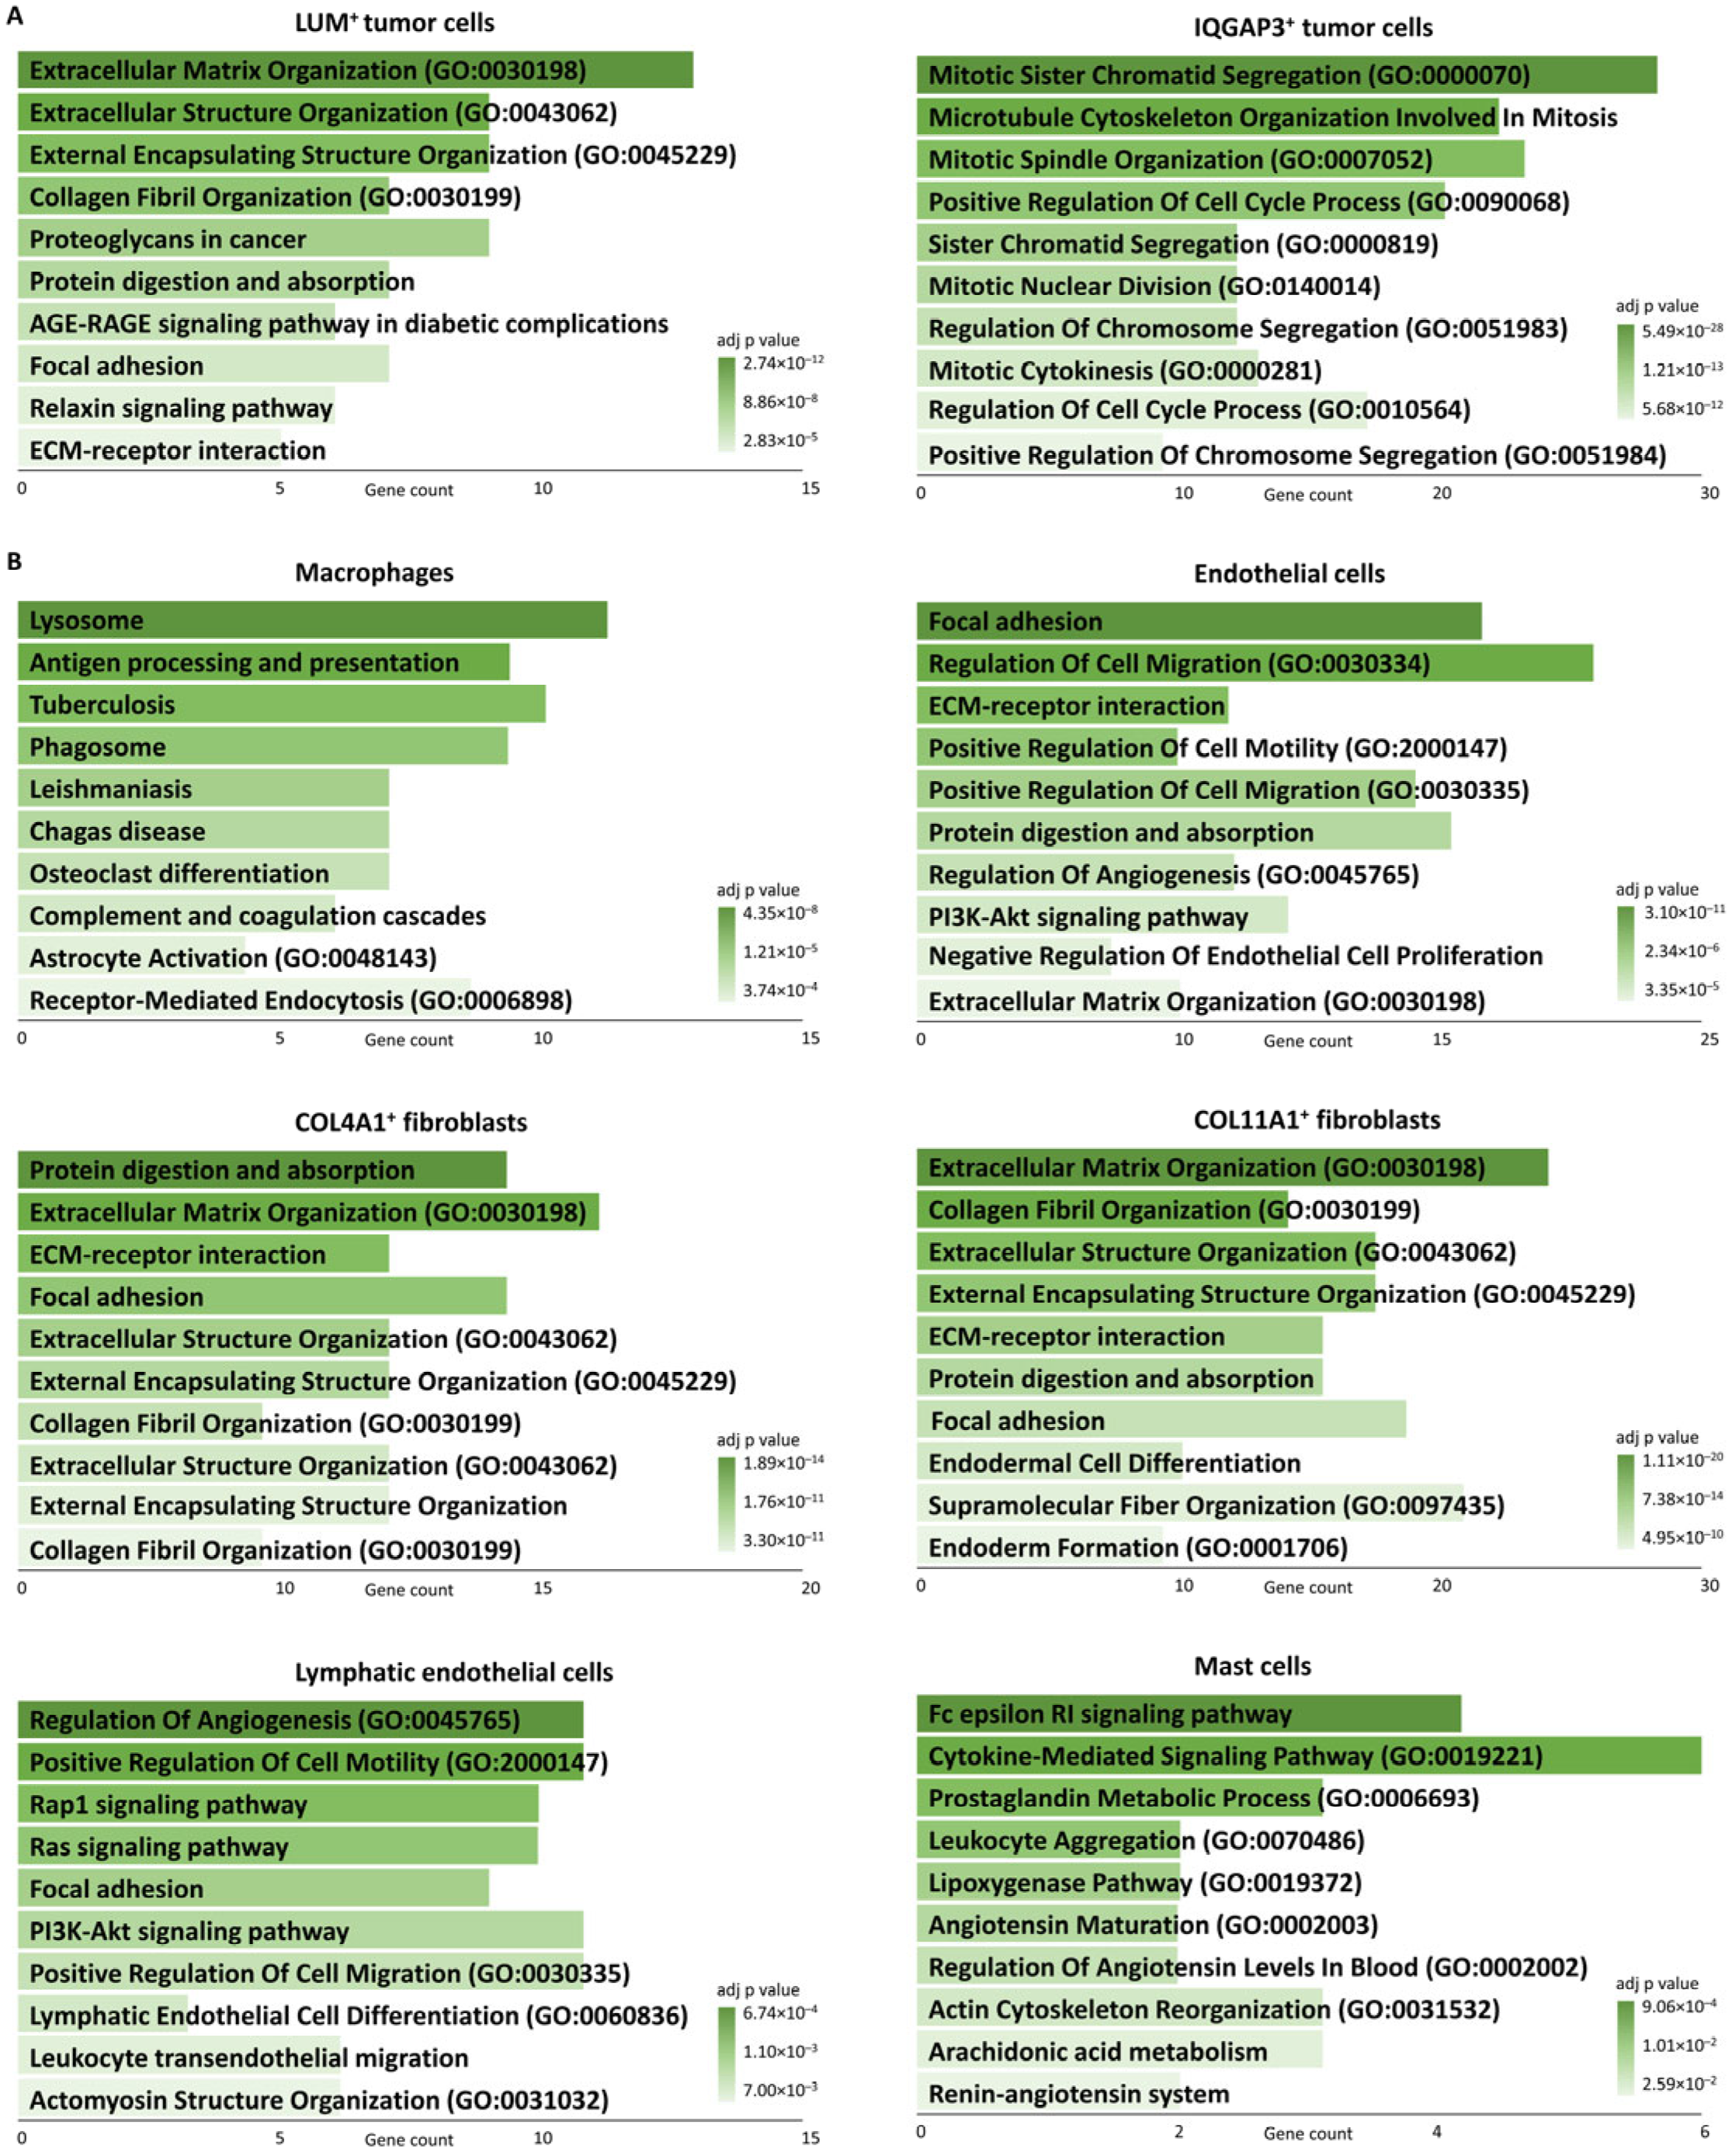

3. Discussion